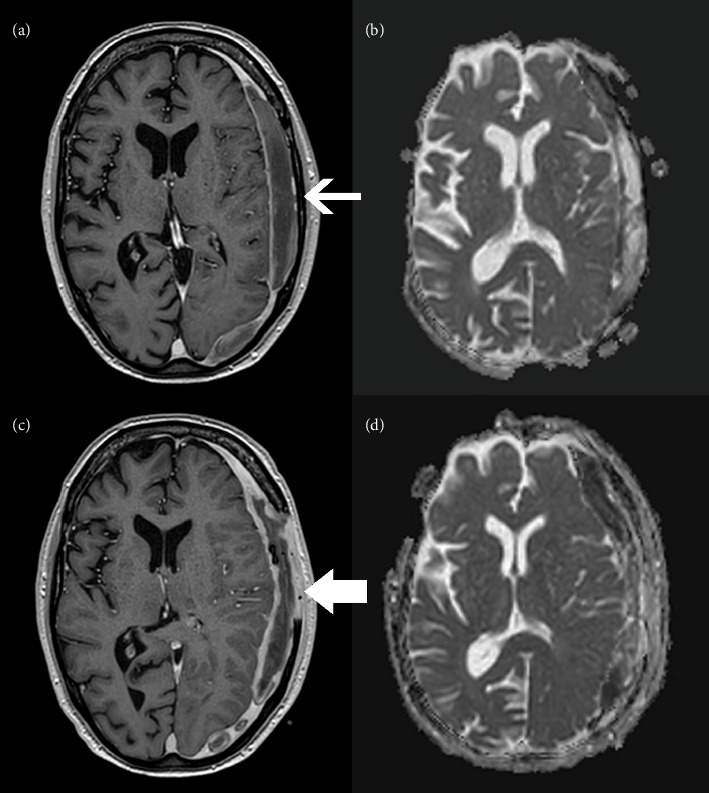

We report the first published case of Erysipelothrix rhusiopathiae causing subdural empyema. This 66-year-old male patient had relevant exposure history including living in a tent in the woods and having direct contact with wildlife. His main symptom which triggered his presentation was diplopia with exam findings consistent with a left partial oculomotor nerve palsy. Initial attempts at less invasive source control via burr holes alone failed. He was treated successfully with craniectomy and aqueous penicillin G with a duration of 6 weeks following surgery. CNS infection as the primary manifestation of Erysipelothrix rhusiopathiae has been reported in only one other case based on our review of the literature. This pathogen demonstrates an ability to manifest infection in many ways and remains susceptible to narrow spectrum beta-lactams.